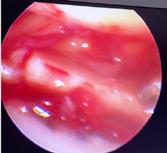

Tratamentul chirurgical este indicat în fracturile cu separare sau înfundare. Momentul optim al intervenției chirurgicale, precum și tipul de osteosinteză ales, sunt strâns legate de leziunile de părți moi, rezultate mai ales în urma fracturilor produse prin traumatisme cu energie cinetică mare. Prezența flictenelor contraindică reducerea deschisă și fixarea internă. Prevenția sau tratarea leziunilor tisulare se poate face prin crioterapie(11), imobilizare sau extensie transcalcaneană urmată de tracțiune osoasă continuă.

În fracturile Schatzker I, fără leziuni de menisc extern asociate este indicată reducerea și osteosinteza percutană cu șuruburi. Dacă leziunea de menisc este evidențiată pe RMN, se poate opta pentru reducere și osteosinteză percutană cu șuruburi asociată cu artroscopie(12), având rol de control al reducerii și curativ pentru leziunea de menisc, sau reducere deschisă și fixare internă cu placă și șuruburi.

La pacienții tineri cu fracturi Schatzker tip II și III se poate opta pentru reducere și osteosinteză percutană cu șuruburi asociată cu artroscopie. O altă variantă este cu grefă osoasă și reducere deschisă cu fixare internă cu placă și șuruburi. Controlul reducerii intraoperator se realizează artroscopic sau cu C arm.

Fracturile tip Schatzker IV, fără leziuni asociate, pot fi tratate cu osteosinteză percutană, iar cele cu leziuni ligamentare sau de menisc, cu reducere deschisă și fixare internă.